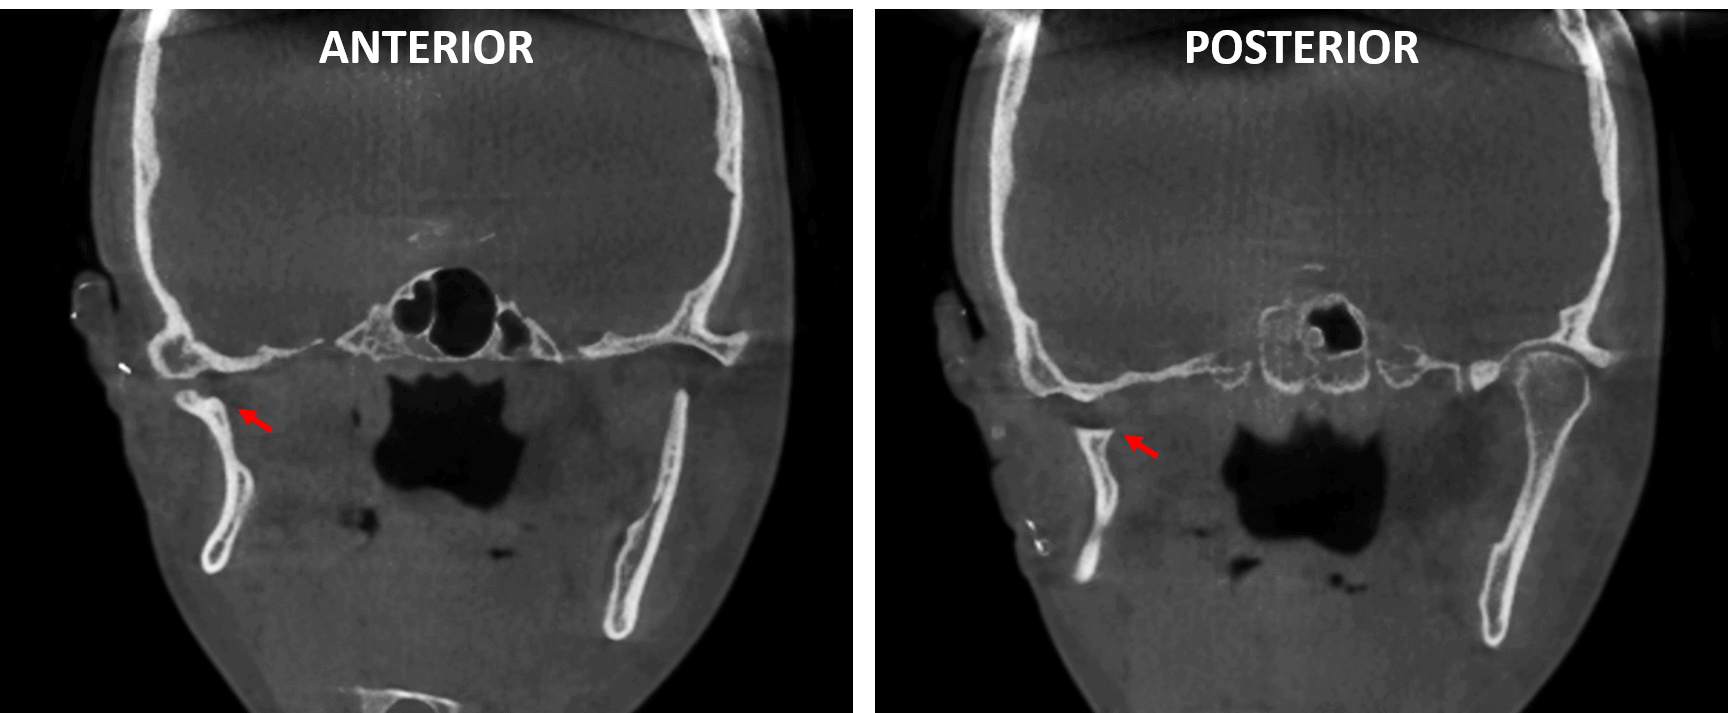

Fig.4

En cortes coronales (Fig.4) se observa comparativamente ambas ramas mandibulares donde observa la adaptación ósea de la mencionada proyección ósea que funge como el cóndilo mandibular derecho (flecha roja). De forma contralateral, se observa la rama mandibular del lado izquierdo.